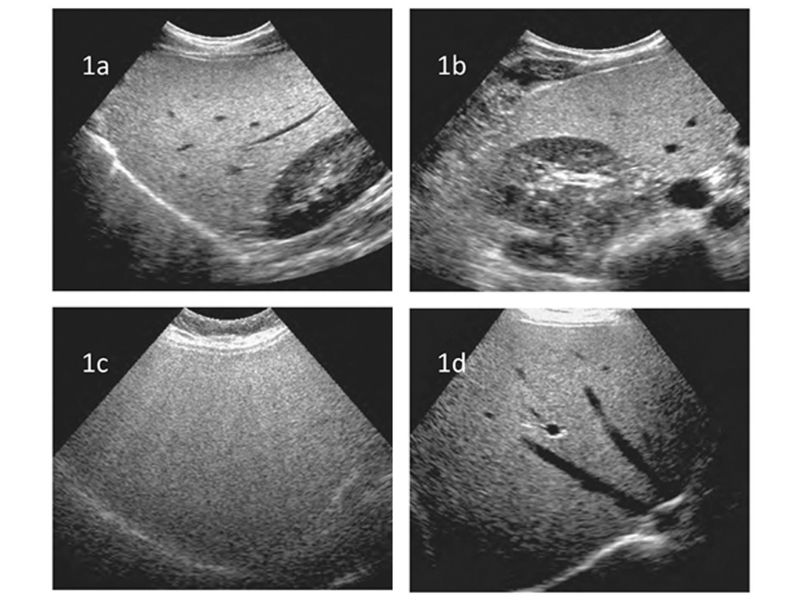

3. Hình ảnh siêu âm gan nhiễm mỡ như thế nào?

Siêu âm là phương pháp chẩn đoán phổ biến, giúp xác định tình trạng gan nhiễm mỡ thông qua các hình ảnh đặc trưng của nhu mô gan. Các đặc điểm hình ảnh siêu âm của gan nhiễm mỡ bao gồm:

- Hình ảnh nhu mô gan sáng và dày hơn (tăng độ hồi âm của nhu mô gan): Mô gan bị nhiễm mỡ phản xạ sóng âm mạnh hơn mô gan bình thường, tạo nên hình ảnh sáng hơn trên siêu âm. Độ hồi âm của gan vượt trội so với vỏ thận hoặc lách. Hình thái gan xuất hiện các đốm sáng rải rác hoặc khu trú.

- Giảm độ nét của cấu trúc gan: Đường bờ của các mạch máu, cơ hoành hoặc tĩnh mạch cửa bị mờ đi. Khả năng phân định chi tiết trong gan suy giảm, đặc biệt ở mức độ nhiễm mỡ cao.

- Kích thước gan thay đổi: Siêu âm có thể phát hiện tình trạng gan to (hepatomegaly) do sự tích tụ mỡ, bờ gan tròn và nhẵn.

Dựa vào tình trạng tăng độ sáng này của nhu mô gan, bác sĩ có thể đánh giá mức độ gan nhiễm mỡ như sau:

- Mức độ 1 (nhẹ): Gan tăng âm nhẹ, hút âm thay đổi không đáng kể, vẫn thấy rõ cơ hoành và đường bờ các tĩnh mạch.

- Mức độ 2 (trung bình): Hồi âm của nhu mô gan lan tỏa mạnh hơn, hút âm gia tăng, giảm khả năng xác định bờ tĩnh mạch trong gan và cơ hoành.

- Mức độ 3 (nặng): Hồi âm của gan lan toả rõ rệt, đường bờ các mạch máu, cơ hoành và một phần nhu mô gan ở phân thùy sau gan phải không còn nhận diện được.